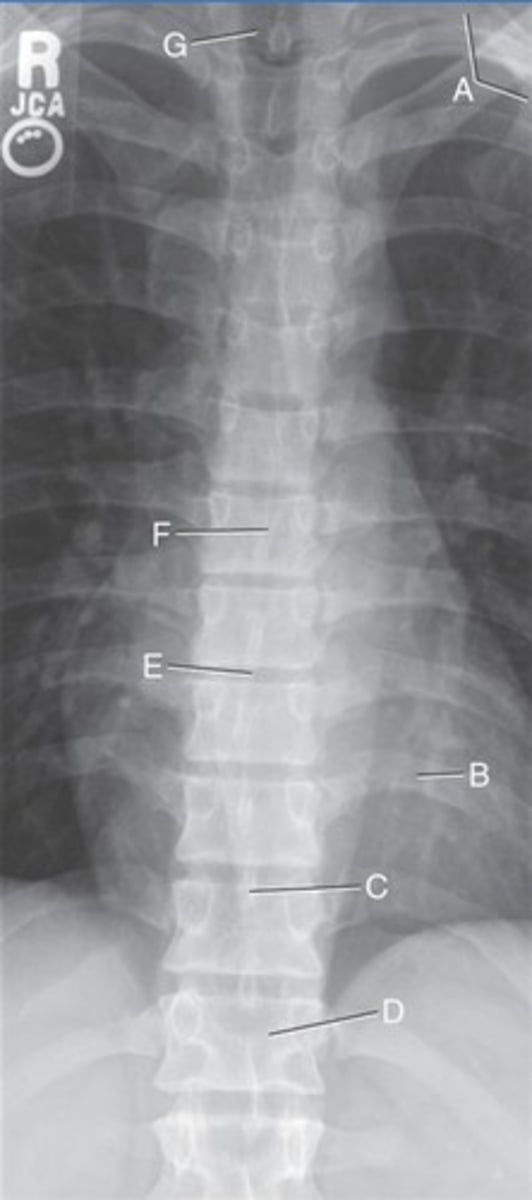

L5 R transverse process

A.

L4 Lower lateral portion

B.

L4 spinous process

C.

L3 R inferior articular process

D.

L4 L superior articular process

E.

L1-2 intervertebral disk space

F.

AP Lumbar

What position?